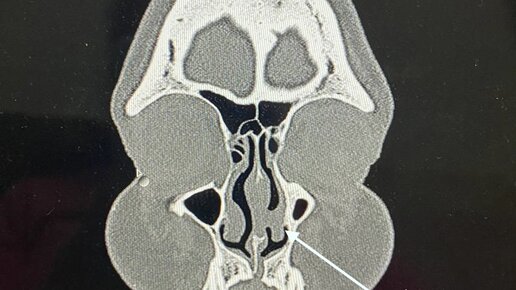

Что такое синехия полости носа? И чем опасно данное заболевание?

Нередким осложнением после риносептопластики, является появление «спаек или сращений» в полости носа. В переводе с греческого, синехия / synecho - «скрепляю, соединяю». Данным термином обозначают различные патологические соединения между соседними органами или поверхностями. Патологическое срастание поверхностей может быть, как врожденного, так и приобретеннного характера: Одним из возможных причин может быть, так же, длительная тампонада полости носа марлевыми турундами. Синехии могут быть односторонние и двусторонние...